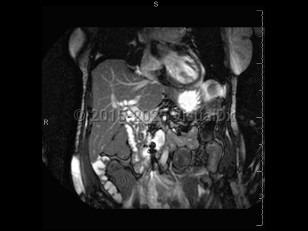

Imaging Studies image of Acute cholangitis - imageId=6839360. Click to open in gallery.  caption: '<span>MRCP image demonstrates  numerous fililng defects in the dilated extrahepatic biliary tree.  Purulent material was found during ERCP. Findings consistent with  cholangitis.</span>'

MRCP image demonstrates numerous fililng defects in the dilated extrahepatic biliary tree. Purulent material was found during ERCP. Findings consistent with cholangitis.